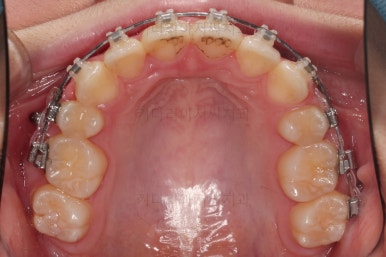

연산동치아교정 이제 전후 사진을 비교해 볼게요.

아래 앞니가 2개인 것이 표시가 안날 정도로 자연스럽게 교합이 맞아졌습니다.

얼굴모습에서도 발치교정이지 윗입술이 많이 들어가지 않게끔 아랫니를 최대한 앞으로 빼둔 상태여서 윗ㅇ입술은 양호하며, 아랫입술은 아래쪽에 깊게 패여있던 주름도 많이 퍼졌습니다.

여러 가지 제약이 많았던 상황이었지만 많은 부분들이 개선된 만족스러운 연산동치아교정 치료였습니다.

이상 아래 앞니가 2개 선천 결손인 환자분을 임플란트 없이 추가 발치로 교합을 맞춰주었던 연산동치아교정 치료사례였습니다.